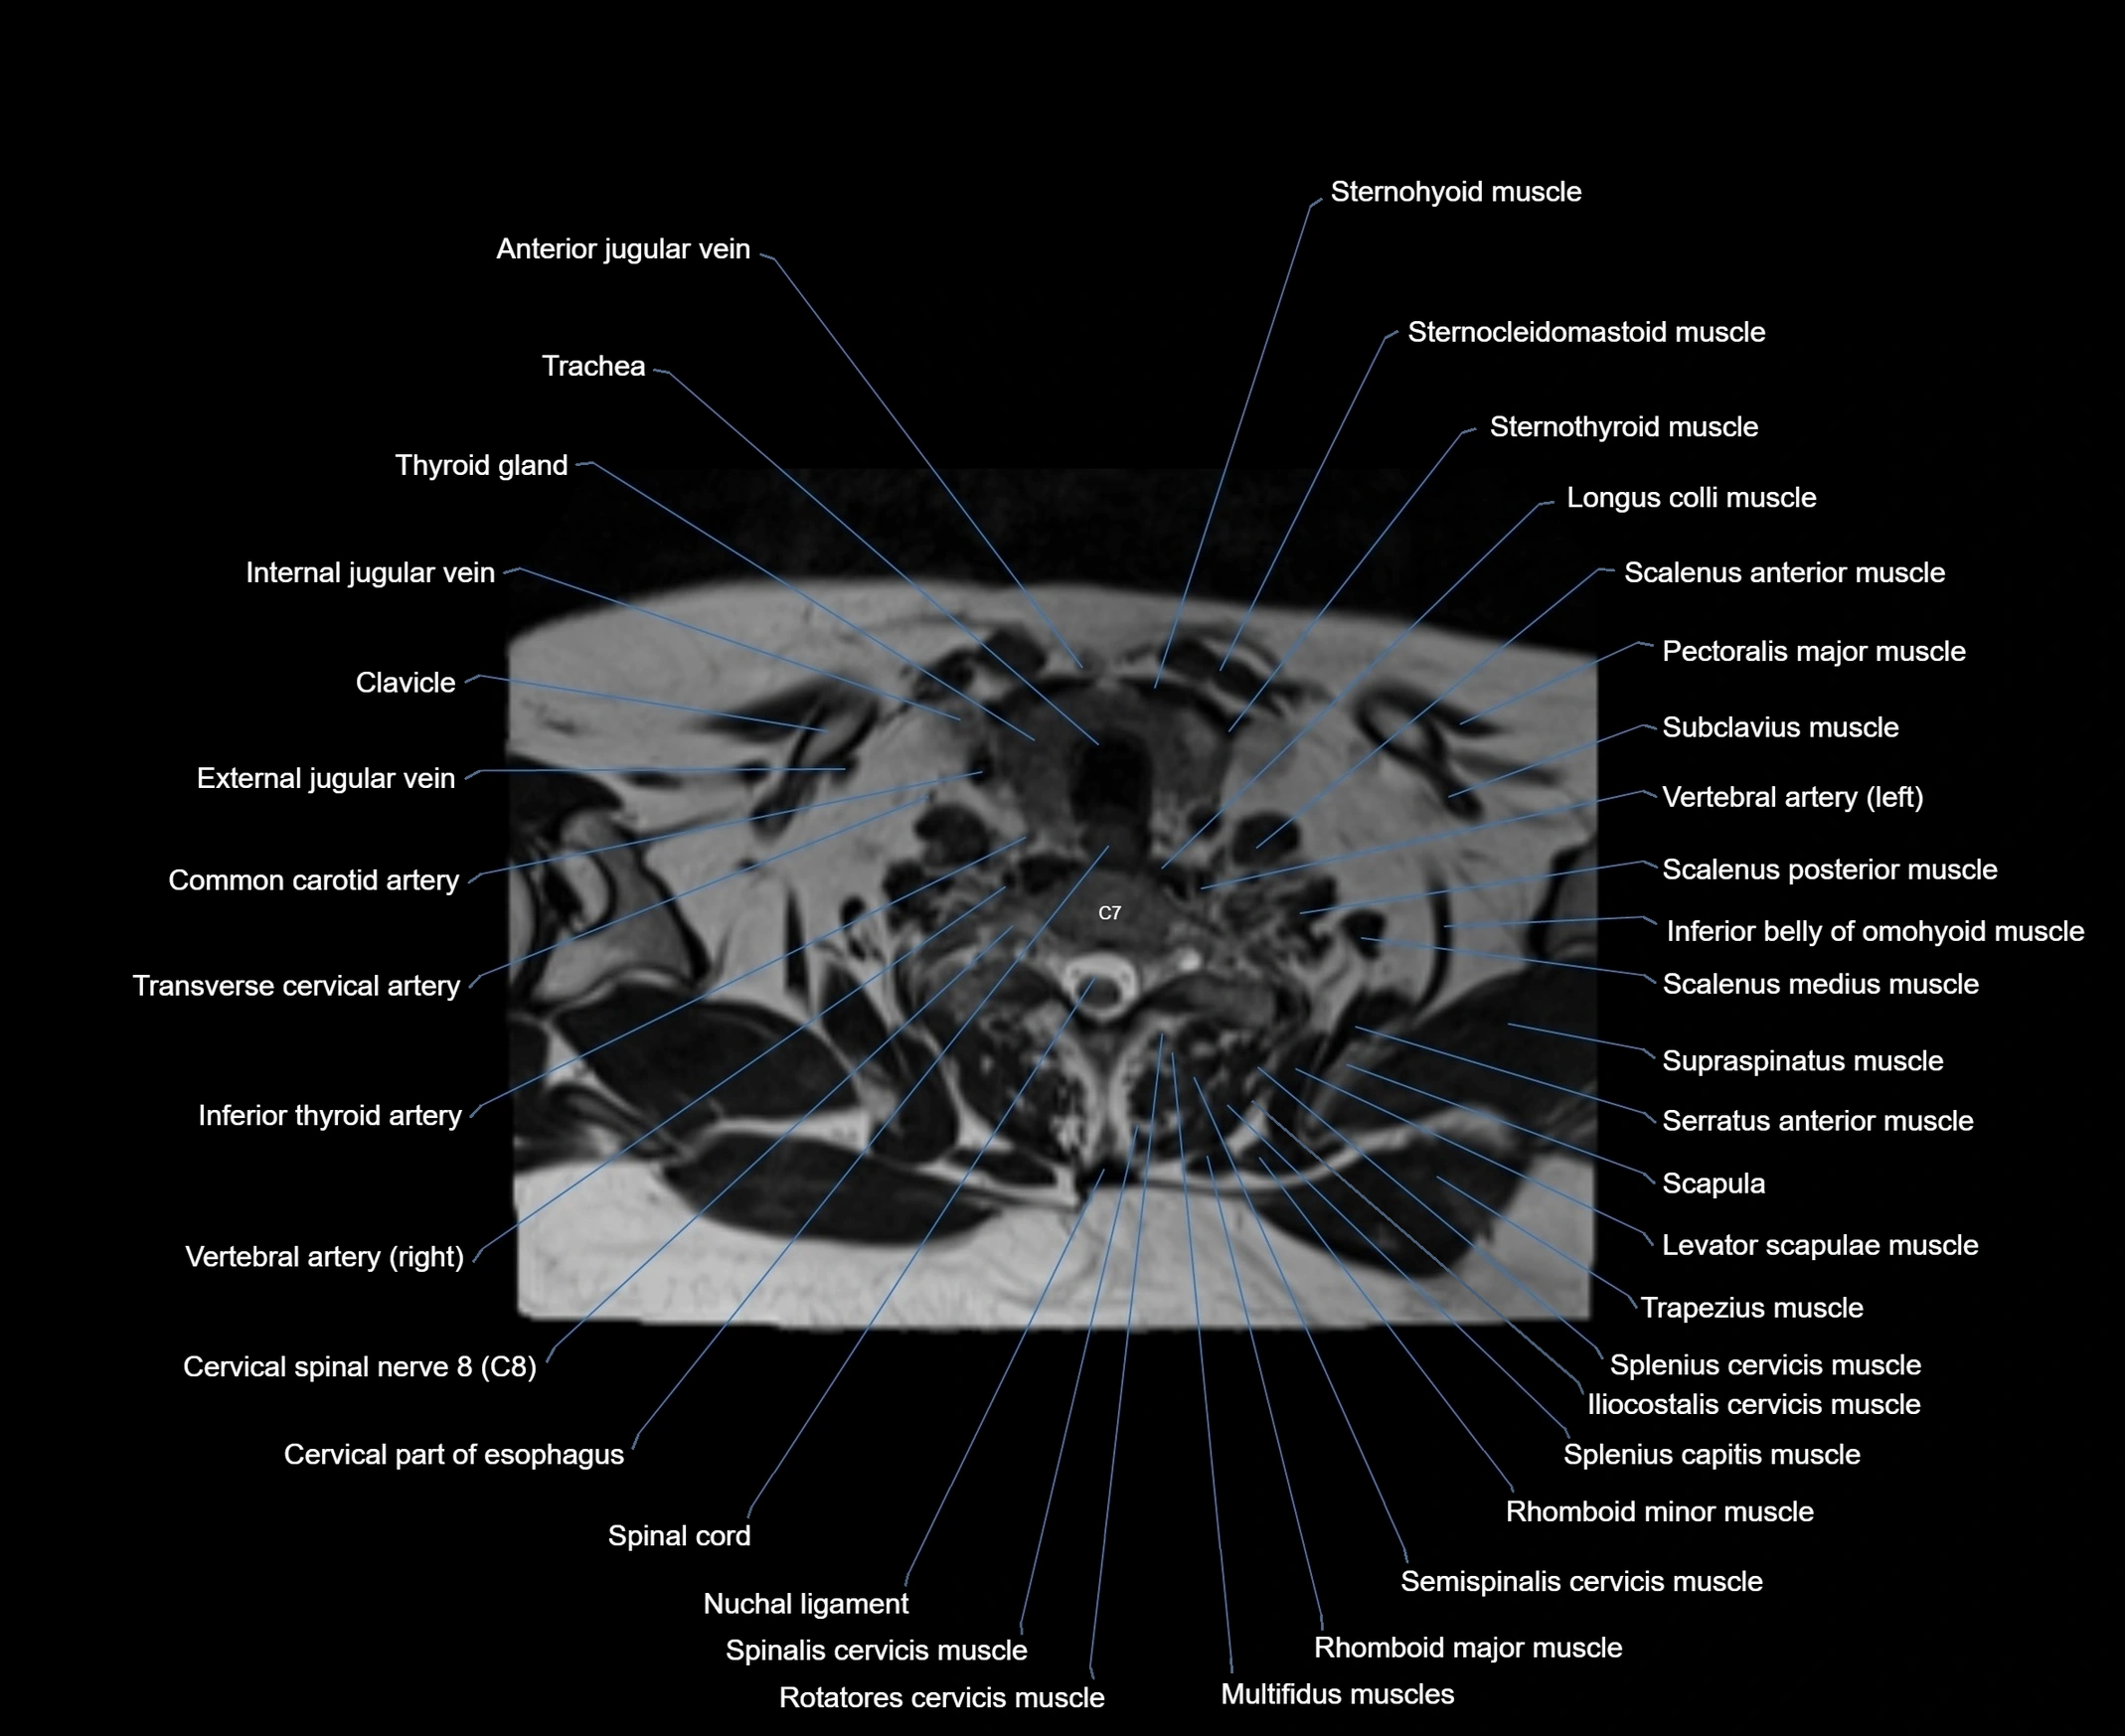

- Anterior jugular vein

- Cervical part of esophagus

- Cervical spinal nerve 8 (C8)

- Clavicle

- Common carotid artery

- External jugular vein

- Inferior belly of omohyoid muscle

- Levator scapulae muscle

- Multifidus muscles

- Pectoralis major muscle

- Rotatores cervicis muscle

- Scalenus anterior muscle (Anterior scalene muscle)

- Scalenus medius muscle (middle scalene muscle)

- Scalenus posterior muscle (Posterior scalene muscle)

- Scapula

- Semispinalis cervicis muscle

- Spinal cord

- Spinalis cervicis muscle

- Splenius cervicis muscle

- Sternocleidomastoid muscle

- Sternohyoid muscle

- Sternothyroid muscle

- Subclavius muscle

- Supraspinatus muscle

- Trapezius muscle